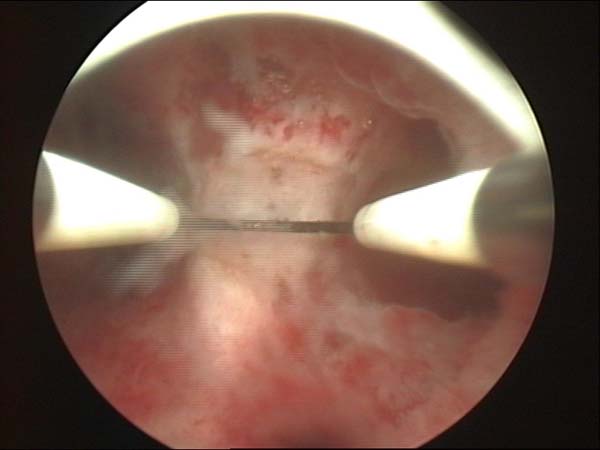

- Hystéroscopie - Hystéroscopie pour l'infertilité

- Résection hystéroscopique d'un septum utérin pour fausses couches à répétition

- Clips vidéo de l’hystéroscopie

- Photos de l’hystéroscopie